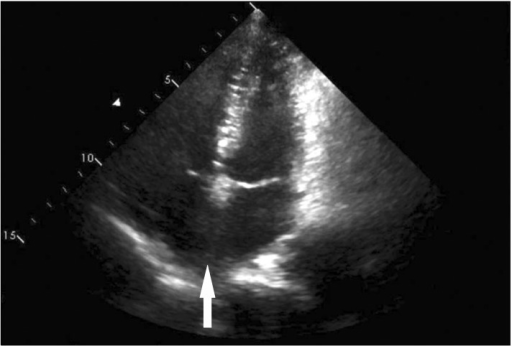

What's the Diagnosis?